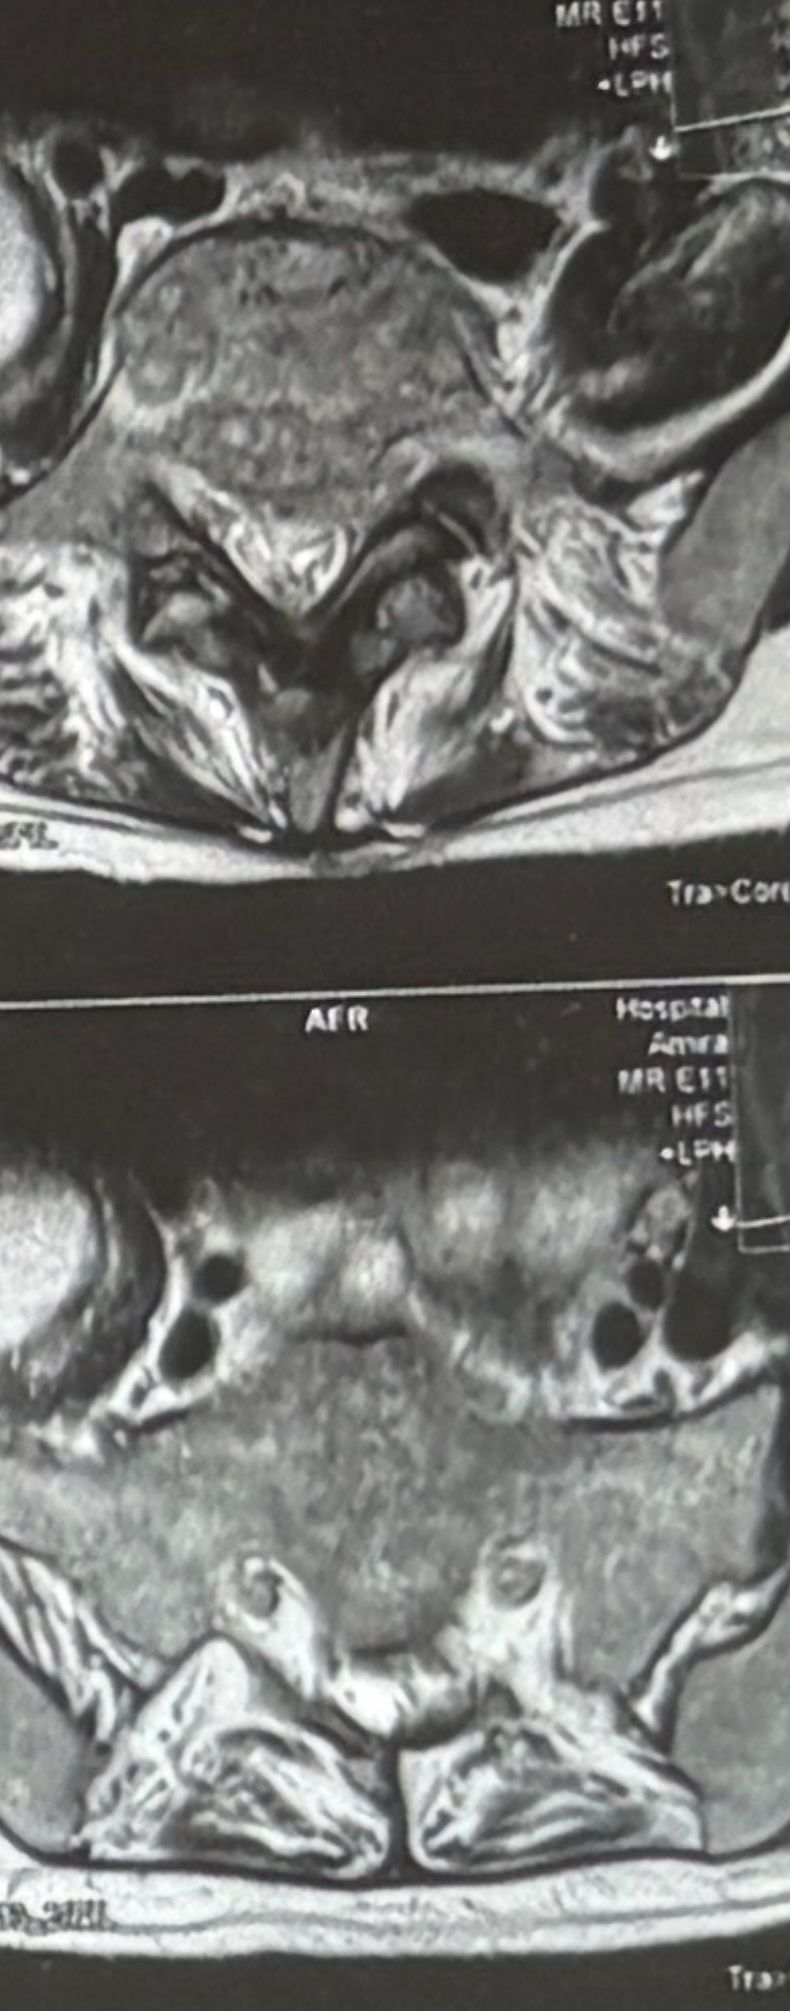

40 yrs old male patient presented to my office who had severe R gluteal pain and radicular pain along R L5-S1 now pain has reduced by 80% in his motor exam had R big toe L5 motor reduced to 4+\5 and R S1 DTR was 0 while L S1DTR was 1+

We did EMG/NCV which showed Mod- sever R L5 S1 irritation without any active axonal loss

I had to decide to refer him for surgery or not patient didn’t have any treatment meanwhile

I ordered new L/S mri

I posted his new mri and old mr

Which was 20 days ago and have posted all below

The first 12 mris had been done 20 days ago

After those first 12 MRIs i have posted new MRIs which were done yesterday

After seeing his new mri and emg/ncv and getting sure his neurological deficit is not active and progressing i told patient he doesn’t need surgery at this time and released him with some advices and exercises